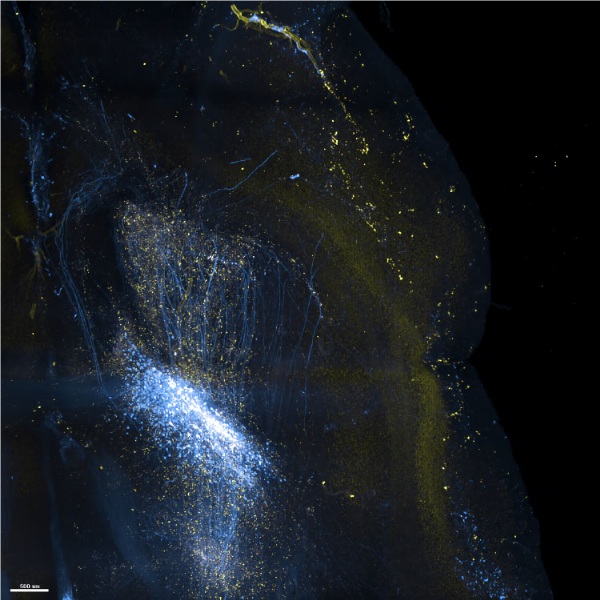

諾倫科技結合專利技術與自有研發團隊,創立3D病理影像技術平台,且為提供高品質、高穩定的3D病理影像,推出一站式的3D全組織病理影像服務。

目前可將厚達1.5cm的小鼠腦與各式鼠類器官進行3D影像掃瞄成像,也能執行2mm的腫瘤組織。

諾倫科技結合專利技術與自有研發團隊,創立3D病理影像技術平台,且為提供高品質、高穩定的3D病理影像,推出一站式的3D全組織病理影像服務。

目前可將厚達1.5cm的小鼠腦與各式鼠類器官進行3D影像掃瞄成像,也能執行2mm的腫瘤組織。